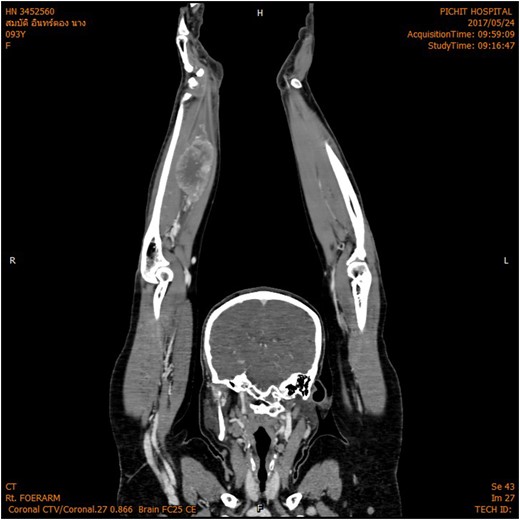

The magnetic resonance imaging (MRI) scan demonstrated a hypervascular mass with multiple feeding vessels located in flexure tendon of right forearm (Fig. 2). Ultrasound-guided biopsy revealed malignant poorly differentiated epithelioid neoplasm with clear cell feature and focal necrosis (Fig. 3). Workup distant metastasis prior operation chest X-ray and intra abdominal were cleared. Bone scan study shows the areas of increased radiotracer accumulation at right seventh of right rib posterolaterallly, L2, right sacroiliac region, proximal part of left humerus and proximal of right femur, multiple foci of osseous metastasis cannot be rule out.

MRI shown hypervascular mass with multiple feeding vessels located in flexure tendon of right forearm.